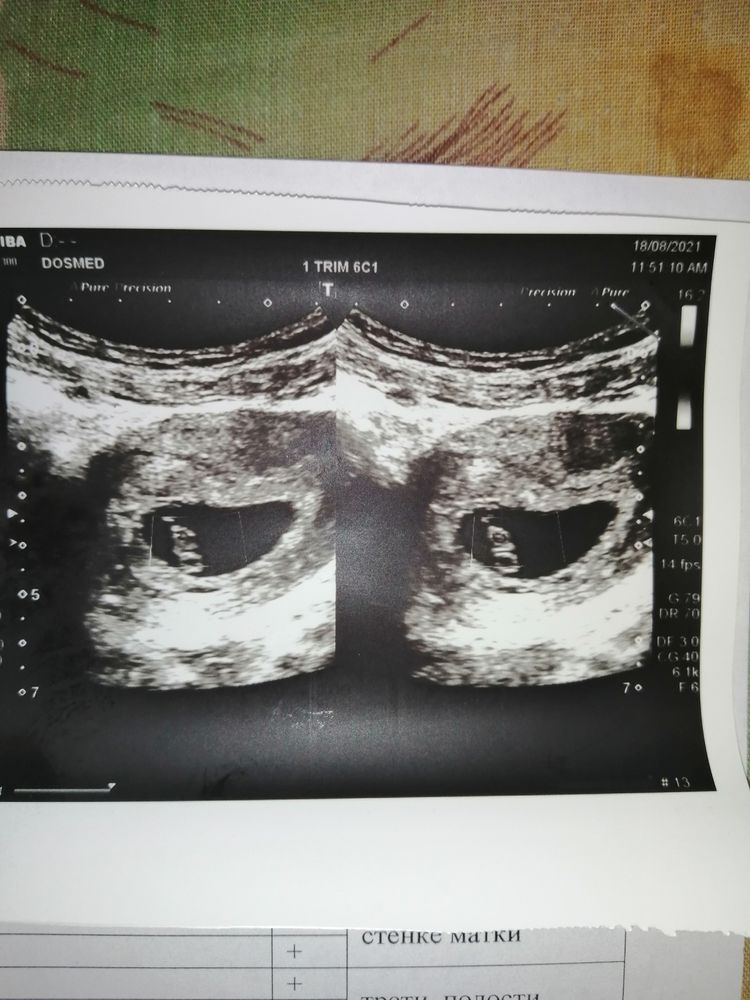

Здравствуйте. Ситуация такая: недели две назад была у гинеколога, поставила угорозу под вопросом. Назначила утрожестан 2 р. в день и витамины. Была до этого коричневая мазня. На второй день после приема лекарства она прекратилась. Сделала контрольное узи 18 числа. Мне сказали, что отслойка сейчас заживает, но не объяснили ни размеров, ни насколько это опасно. Только то, что она была. Врач сказала, что утрожестан надо принимать весь первый триместр. Через 4 недели снова на УЗИ. Кто разбирается, можете сказать, все плохо или нет? Заранее благодарю